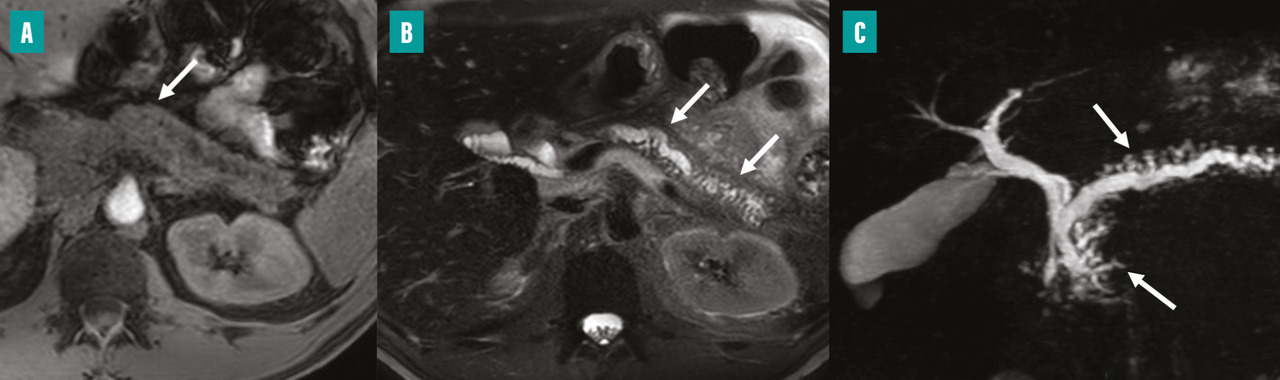

Imagerie par résonance magnétique et cholangio-pancréatographie-IRM, examens de référence

L’imagerie par résonance magnétique (IRM) en particulier lorsqu’elle est associée à la cholangio-pancréatographie-IRM (CP-IRM), est considérée comme l’examen d’imagerie diagnostique de référence pour la pancréatite chronique. Elle permet de détecter des calcifications, l’atrophie pancréatique, ainsi qu’une obstruction ou une dilatation des conduits.

La CP-IRM, fondée sur des séquences fortement pondérées en T2, permet une visualisation dédiée et non invasive des conduits biliopancréatiques en deux et trois dimensions et elle est plus sensible que la TDM pour l’évaluation des anomalies canalaires.

Dans les formes précoces de pancréatite chronique, l’IRM peut révéler une hypo-intensité du signal pancréatique sur les séquences pondérées en T1 avec suppression du signal graisseux (perte de l’hypersignal T1 physiologique de la glande), un retard et un aspect hétérogène de rehaussement du parenchyme pancréatique (lié à la présence de fibrose) ainsi qu’une dilatation des conduits secondaires.

Dans les formes plus avancées, la CP-IRM met en évidence une atrophie plus marquée de la glande pancréatique, avec aspect en hyposignal T1, des dilatations irrégulières moniliformes du conduit pancréatique principal et des dilatations en «  flammèches  » des conduits secondaires (fig. 3).